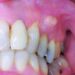

দাঁত ক্ষয়:

গর্ভাবস্থায় দাঁত ক্ষয় হওয়ার ঝুঁকি বেড়ে যায়। কারণ-

১) দাঁত ব্রাশ করার সময় বমি ভাব হওয়ার কারণে কেউ কেউ প্রতিদিন দাঁত ব্রাশ করতে চান না। অনেকে আবার এ সময় শারীরিক, মানসিক ও পারিপার্শ্বিক ধকলে অতিমাত্রায় ক্লান্তি বোধ করার কারণে মুখ ও দাঁতের যত্নে অবহেলা করে বসেন।

২) সকালে বমি হলে তার সাথে পাকস্থলীর অ্যাসিড মুখ দিয়ে বেরিয়ে আসার ফলে দাঁতের বহিরাবরণ (এনামেল) ক্ষয় (erosion) হতে পারে।

গর্ভাবস্থায় হরমোন নিঃসরণে ব্যাপক পরিবর্তন আসে। এর মধ্যে বিশেষত ইস্ট্রোজেন ও প্রোজেস্টেরনের প্রভাবে মাড়ি থেকে রক্ত বেরোনো, ফুলে যাওয়া, মাড়ি ব্যথা, দাঁত শিরশির- এ ধরণের উপসর্গ দেখা দেওয়া খুবই কমন। এছাড়া গর্ভধারণের আগে যদি মাড়িতে প্রদাহ থাকে তাহলে গর্ভাবস্থার ২য় মাস থেকেই তা তীব্রতর রূপ নিতে থাকে!